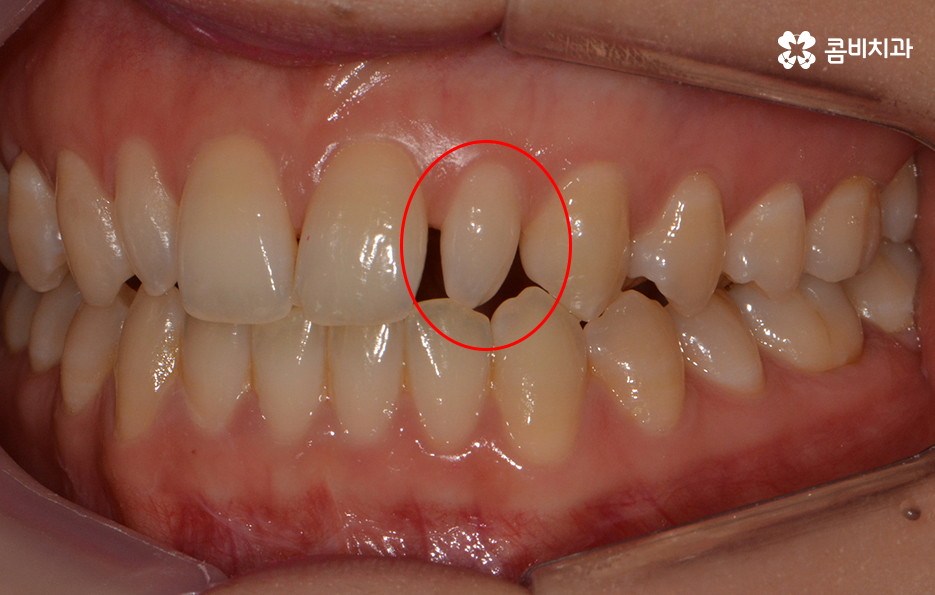

파란 원 - 치아의 깨짐, 빨간 원 - 왜소치

왜소치란? - 일반적인 치아에 비해 비정상적으로 작은 치아를 의미 합니다. 왜소치가 앞니 부분에 위치한 경우 치아가 벌어져 보이거나 심미적인 부담감을 느끼실 수 있습니다.

전체적인 치열 상태가 비교적 가지런한 편이었기 때문에

약 1년 정도 클리피씨교정을 통해서 치열과 교합 개선이 진행 되었습니다.

치열이 가지런하게 정렬이 된 상태에서 앞니 깨짐,

왜소치에 대해서 올세라믹이 진행되었습니다.